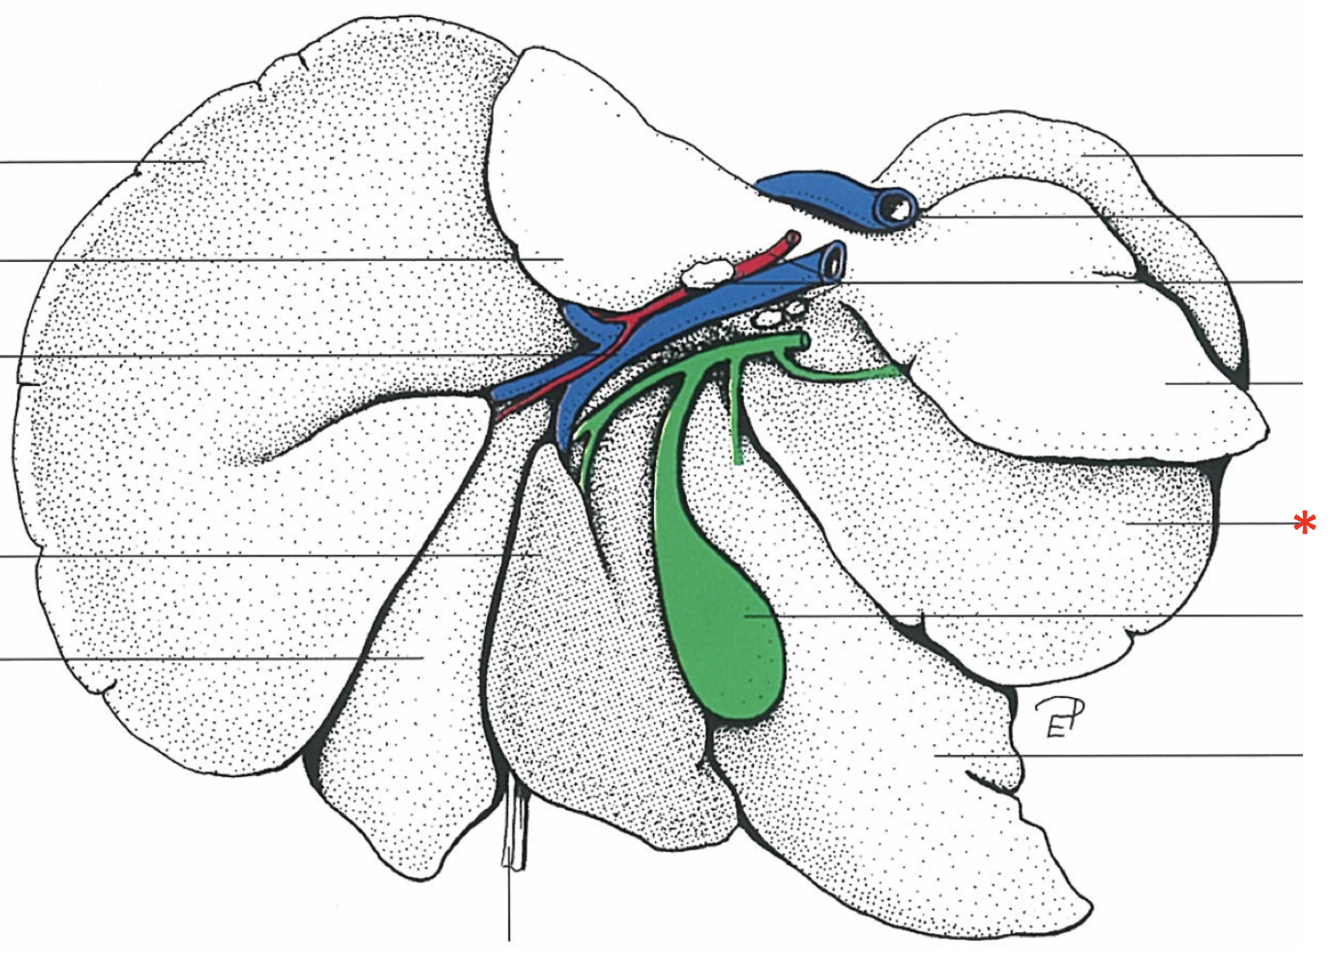

What is shown? Give the Aspect

Liver of a Cat

Fascies visceralis

Dorsal Aspect

Area nuda

- Not covered by serous membrane